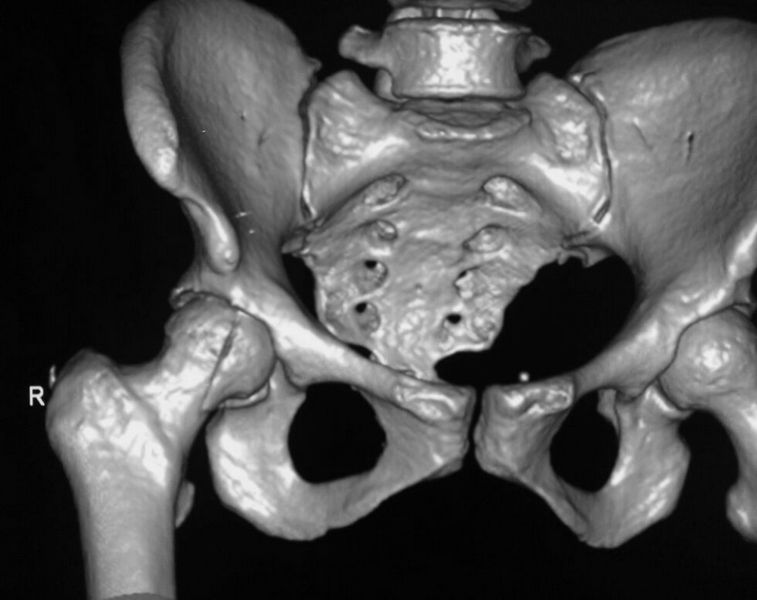

За праздники поступил еще один Pipkin IV. Женщина 30 лет, пострадала в ДТП

(пассажир). Сочетанная травма (ISS 25). Множественные переломы ребер с двух

сторон с пневмотораксом  и пневмомедиастинумом. Закрытый перелом пилона

справа. Задний переломо-вывих головки правой бедренной кости (Pipkin IV).

Ожирение III- IV  степени. Пацинентка в реанимации, состояние остается

тяжелым.

правой нижней конечности в день поступления. КТ контроль показал довольно

сносную картину результата репозиции. Отломок головки оставался в полости

сустава во время вывиха, т.к. видимо сохранилось прикрепление со связкой.

На КТ остается широкой суставная щель, что косвенно может указывать на

интерпозицию мягкими тканями, либо "встать на место" мешает медиальный

отломок головки.